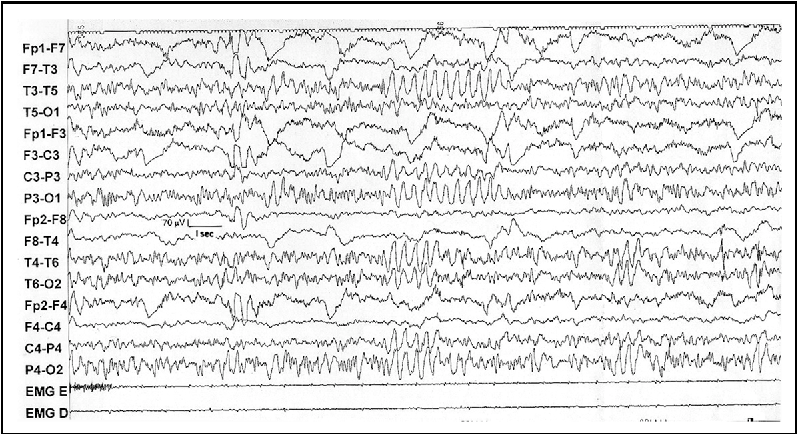

EEG waveform and diagnosis

Triphasic waves

Frontally dominant, anterior to posterior phase lag, 2.5 Hz

Hepatic encephalopathy, progression of encephalopathy and elevated ammonia levels, metabolic abnormalities,